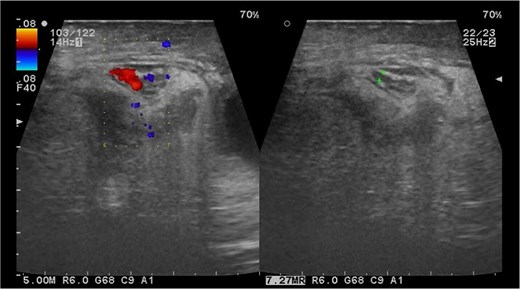

Paraclinical studies revealed leukocytosis of 18 thousand at the expense of >85% neutrophils. Ultrasound of the inguinal region revealed a right testicle of normal dimensions with increased peritesticular fluid, a hernial ring of 39 × 28 mm with passage of intestinal loops, mesentery, and vascular structures which is not reducible during the examination (Fig. 1).